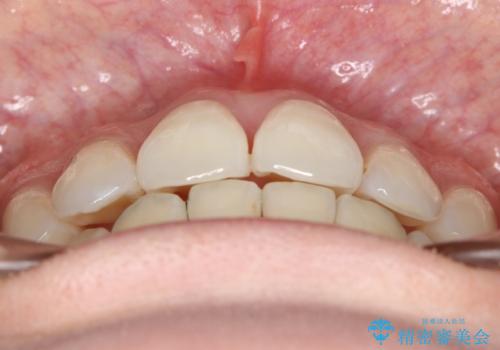

裏側装置で目立たず矯正!

- 治療計画

- 歯のガタつきと出っ歯感を治したいとの主訴でご来院され、ハーフリンガル装置を希望なさったため、検査を行ったうえで上下左右4番目の歯を抜歯し歯列を内側に引っ込めつつ叢生の改善を行うこととなりました。

フルリンガル(上下とも裏側)で治療するよりも費用が抑えられ、治療期間も伸びにくい傾向にあります。また、下顎の舌側に装置がないおかげで口内炎や発音障害もフルリンガルに比べて少ないとされています。

ただし、上下とも表の装置に比べると治療期間・費用共に劣る傾向にあります。